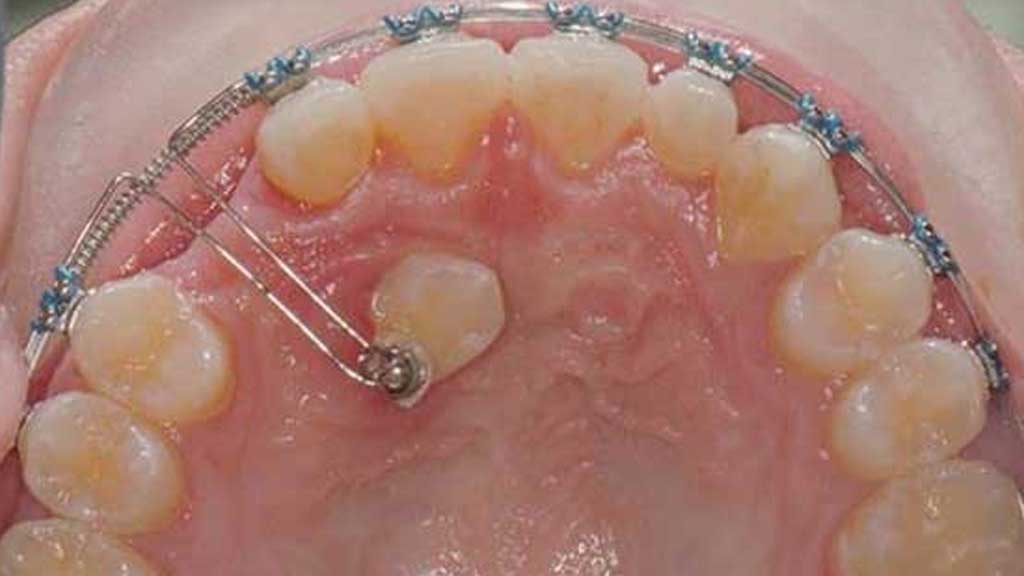

مینی اسکرو (در موارد خاص)

اگر دندان نیاز به حرکت دقیقتری داشته باشد، ممکن است از مینی اسکرو کمک گرفته شود.